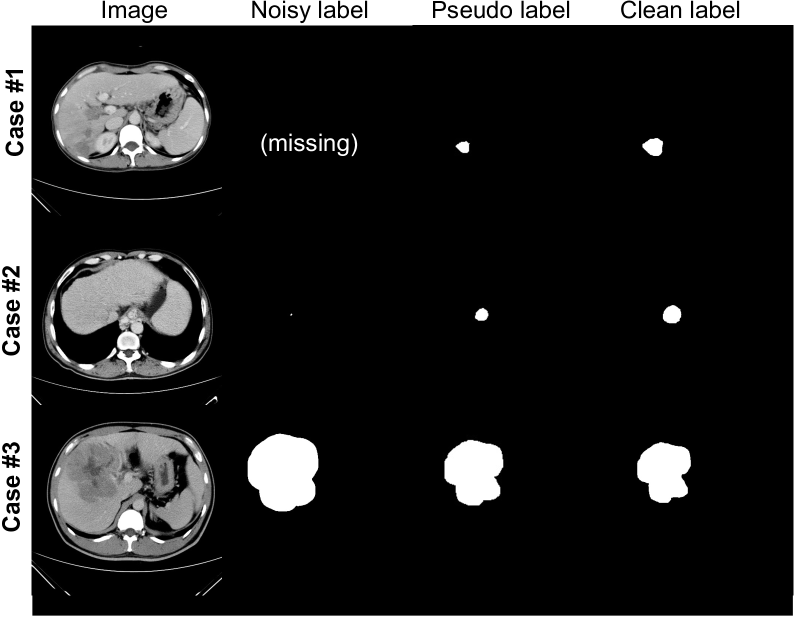

Figure 7: Examples of pseudo labels produced by LCM.

Effectiveness of LCM: We first add LCM to the baseline to assess its effectiveness, whose specific structure is described in Section 2.3. After the warm-up training, LCM indiscriminately corrects all samples every 5 epochs without preserving clean samples. Fig. 7 illustrates several examples of cleansed labels produced by the LCM, demonstrating its effectiveness in correcting both missing labels (Case #1) and boundary noise (Cases #2 and #3). Table 4 provides the corresponding quantitative results, which shows that the LCM improves the segmentation performance of the B-model by +1.36% (in DSC) and also enhances the stability of the baseline, resulting in a +2.53% (in DSC) improvement in the performance of the L-model.